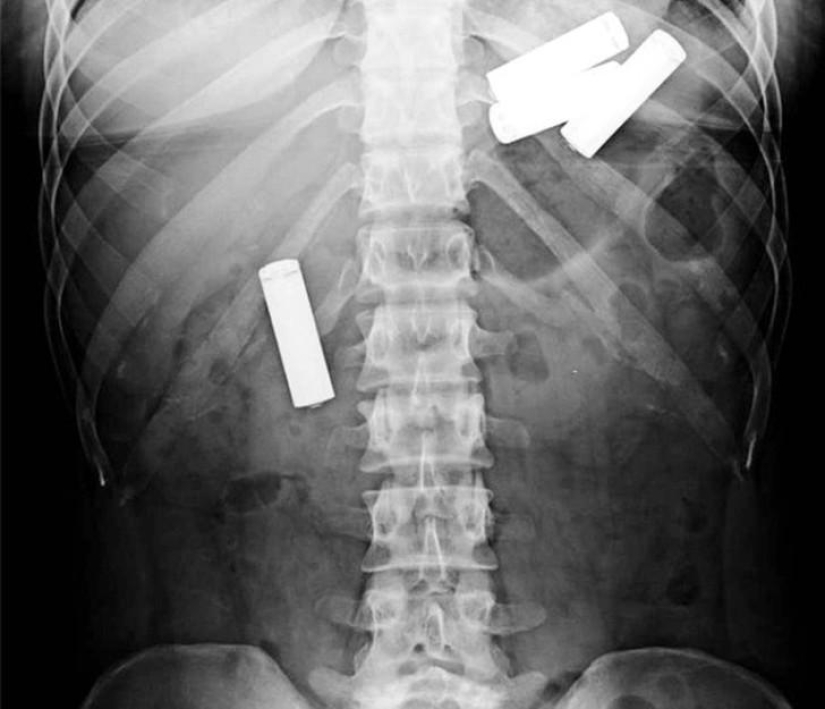

¡Y aquí están las pilas!